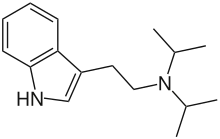

| DiPT | artificial | H | CH(CH3)2 | CH(CH3)2 | N,N-diisopropyltryptamine | 14780-24-6 |